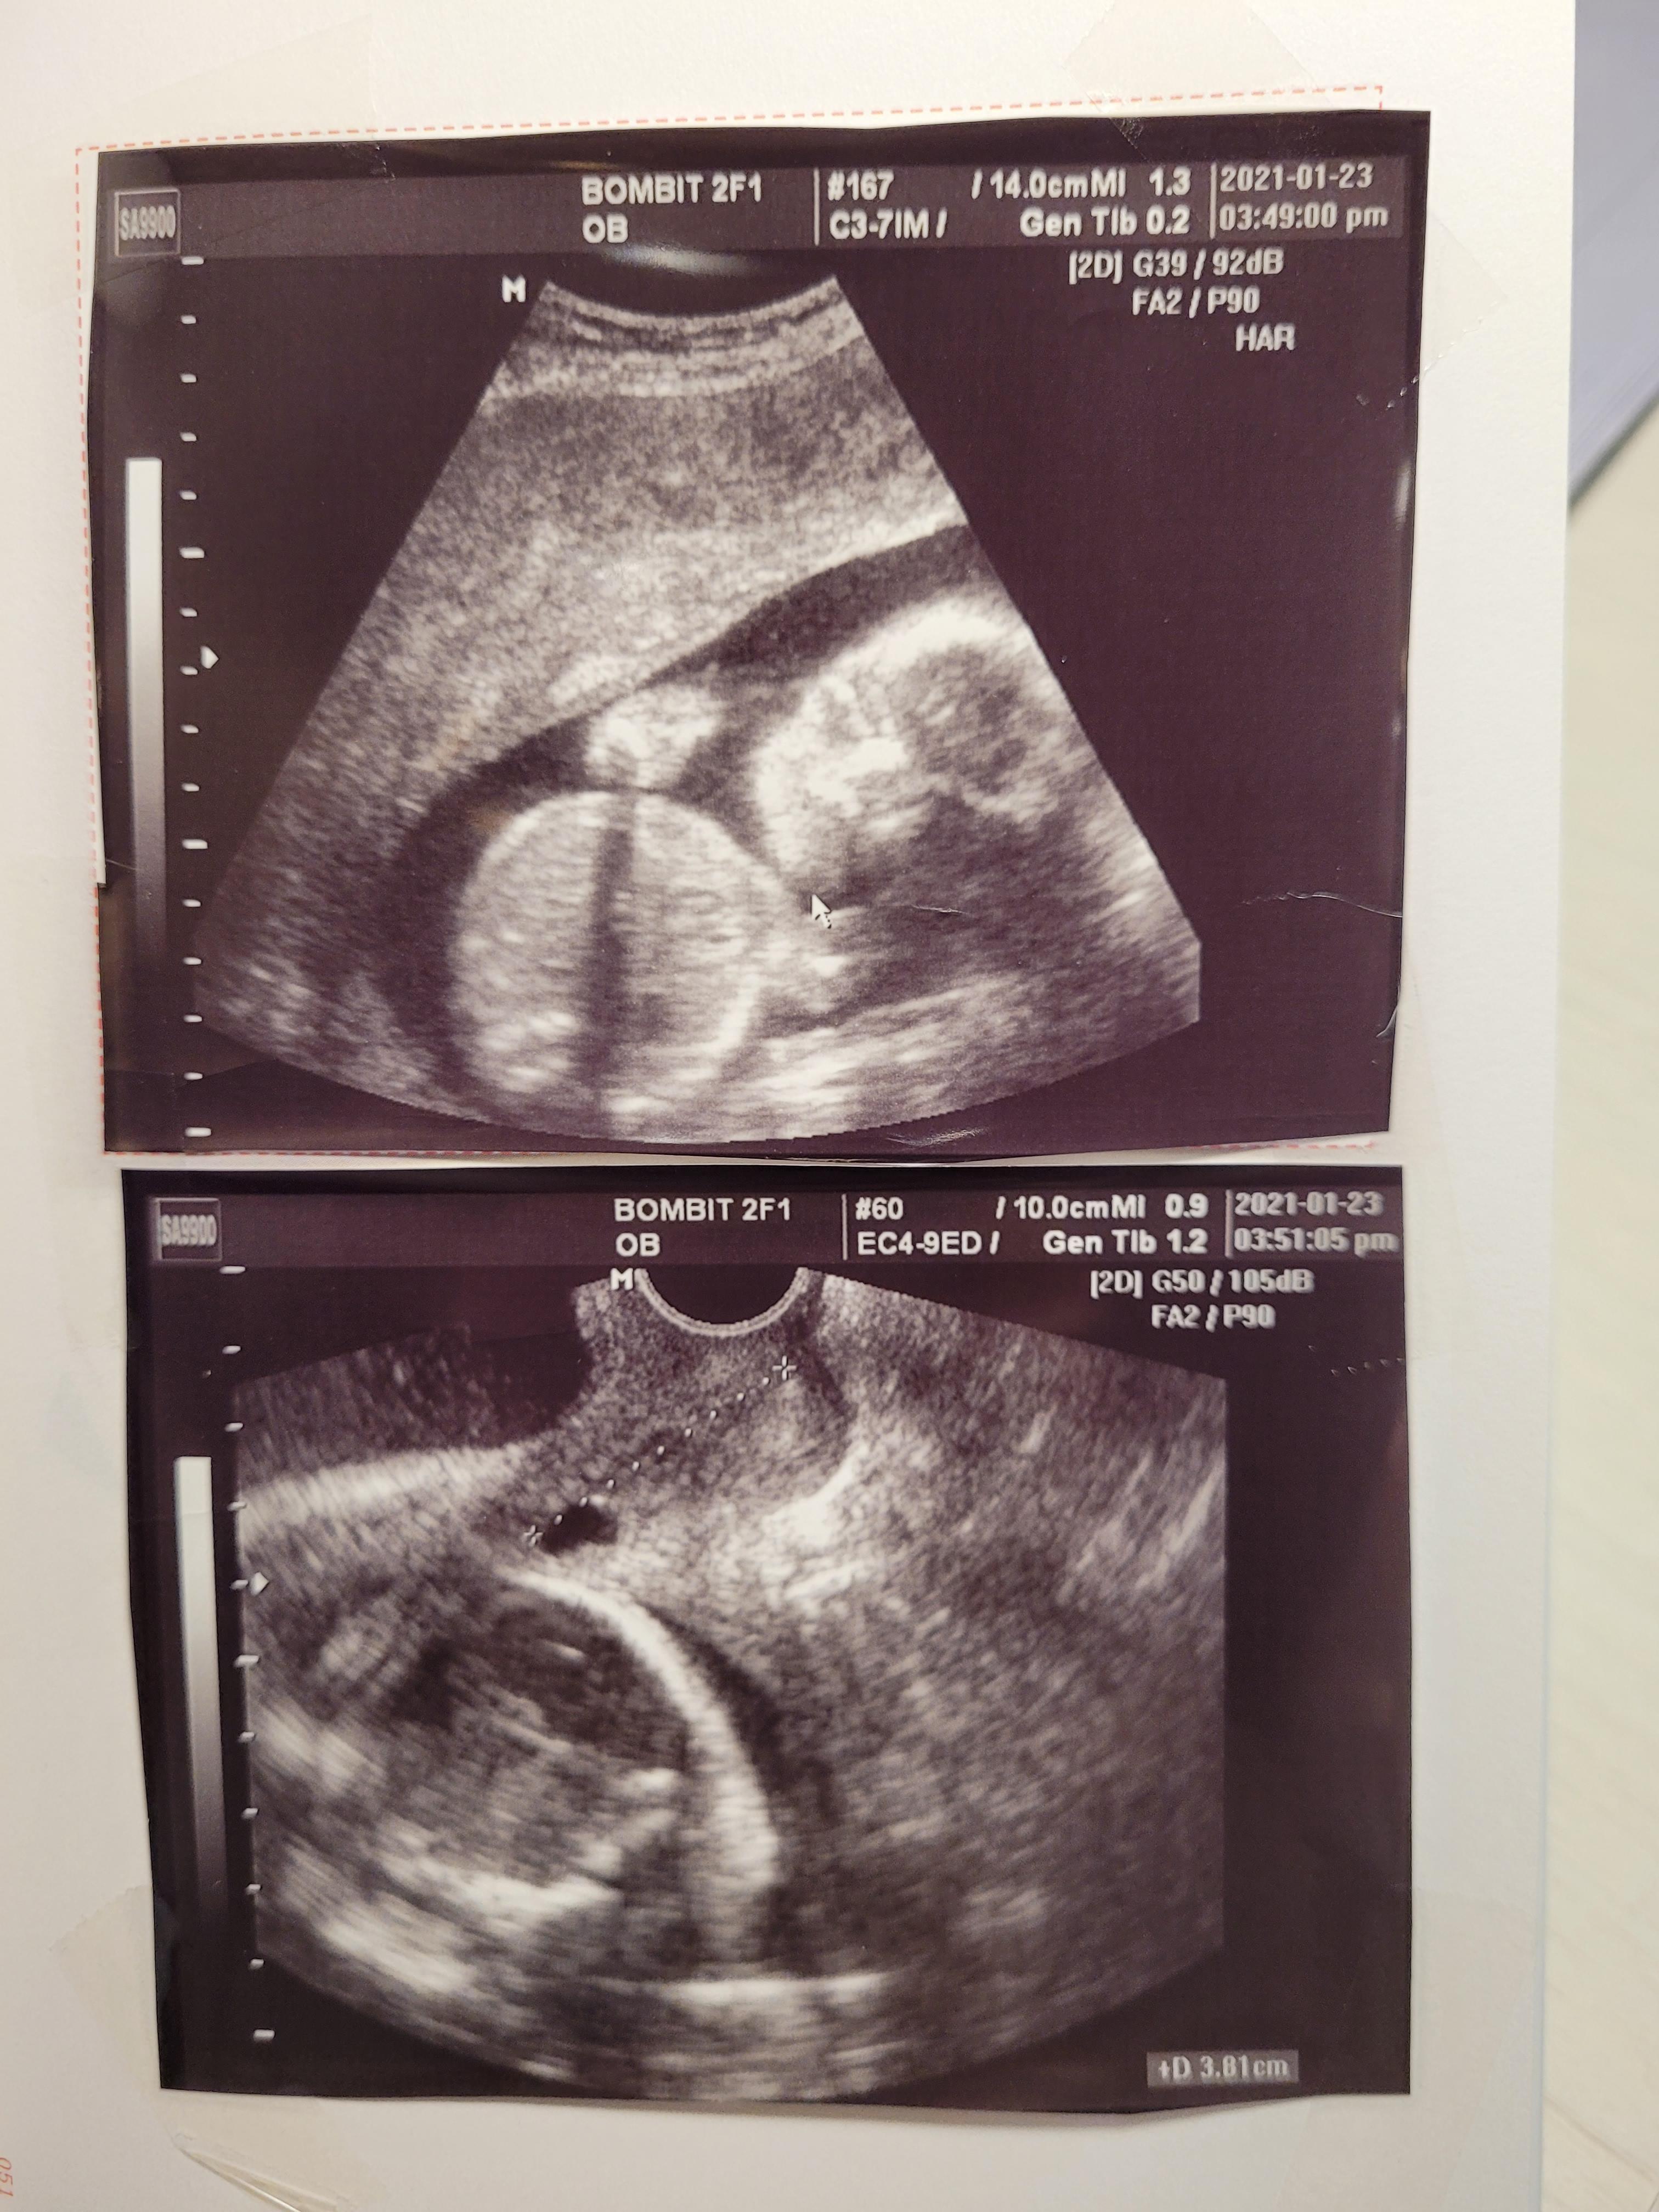

머리부터 시작해서 발끝까지 정말 꼼꼼하게 봐주십니다.

손발, 눈코입은 물론이고요. 뇌초음파, 동맥 등등 혈관, 양수량, 척추 등등

주치의 진료실로 와서, 다시 초음파로 아기 한번 더 확인하고,

질초음파로 경부길이도 잽니다.

저는 약 3.8cm였는데, 위험한 수준은 아니지만 늘 조심하라고 하셨어요.

경부길이도 중요하지만 두께나 강도도 중요한데, 경부가 얇다고요.

임신초기부터 무리한건 하지않았는데, 중기부터 출산일까지도 늘 조심하며 지내야할것 같아요.